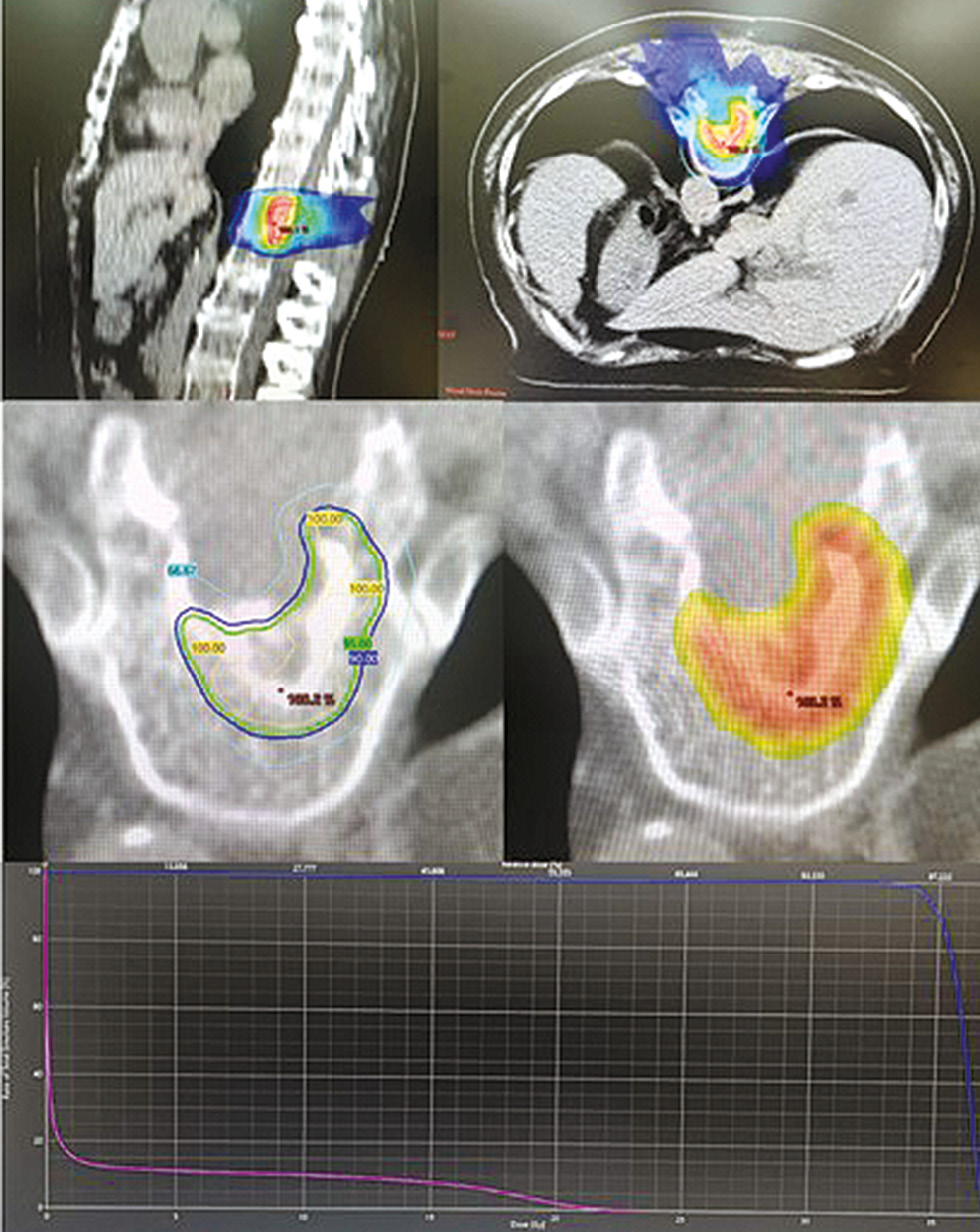

CT topometry was performed in a prone position with the head and feet fixed, with a 5 mm increment. Following target volume contouring and dosimetry (Fig. 3), a decision was made jointly with the Blokhin National Medical Research Center of Oncology to perform stereotactic radiotherapy of the residual tumor in the Th12 vertebra. The single dose was 9 Gy No. 5 daily, up to the total dose of 45 Gy, which corresponds to 166 isoGy when calculated using a linear quadratic model (LQM) with α/β of 2.45 Gy. The therapy was administered in a daytime hospital, using the Varian TrueBeam linear electron accelerator, in volumetric modulated arc therapy (VMAT) mode. The GTV to PTV margin was 0.3 cm; Dmax for the spinal cord was 23.16 Gy; D 0.15 cm3 was 21 Gy. The irradiation target was positioned daily using cone beam computed tomography (CBCT). The patient was discharged on Day 5 after the start of external beam radiotherapy (the day of the last fraction); no adverse events were reported.

Fig. 3. Dose distribution in the radiation volume. Dose-volume (DVH) histogram, spinal cord (lower curve, pink) and PTV (upper curve, blue).

Рис. 3. Распределение дозы в объёме облучения. Гистограмма доза-объём (DVH), спинной мозг (нижняя кривая, розовый цвет) и PTV (верхняя кривая, синий цвет).